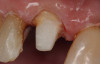

A Class IN maxillary bicuspid was previously restored with a fiber post and an all-porcelain crown (Figure 1). The forces of the oral environment resulted in fracture of the fiber post and crown failure. The remaining fiber post in the root was removed, and anti-rotational areas were prepared for a cast post (Figure 2). A gold cast post was constructed at a dental laboratory, using an indirect technique (Figure 3). A porcelain-fused-to-metal (PFM) crown was constructed with a bevel finish to provide a ferrule and reduce forces on the post (Figure 4 and Figure 5).

Figure 4  The cast post was cemented.

Figure 4